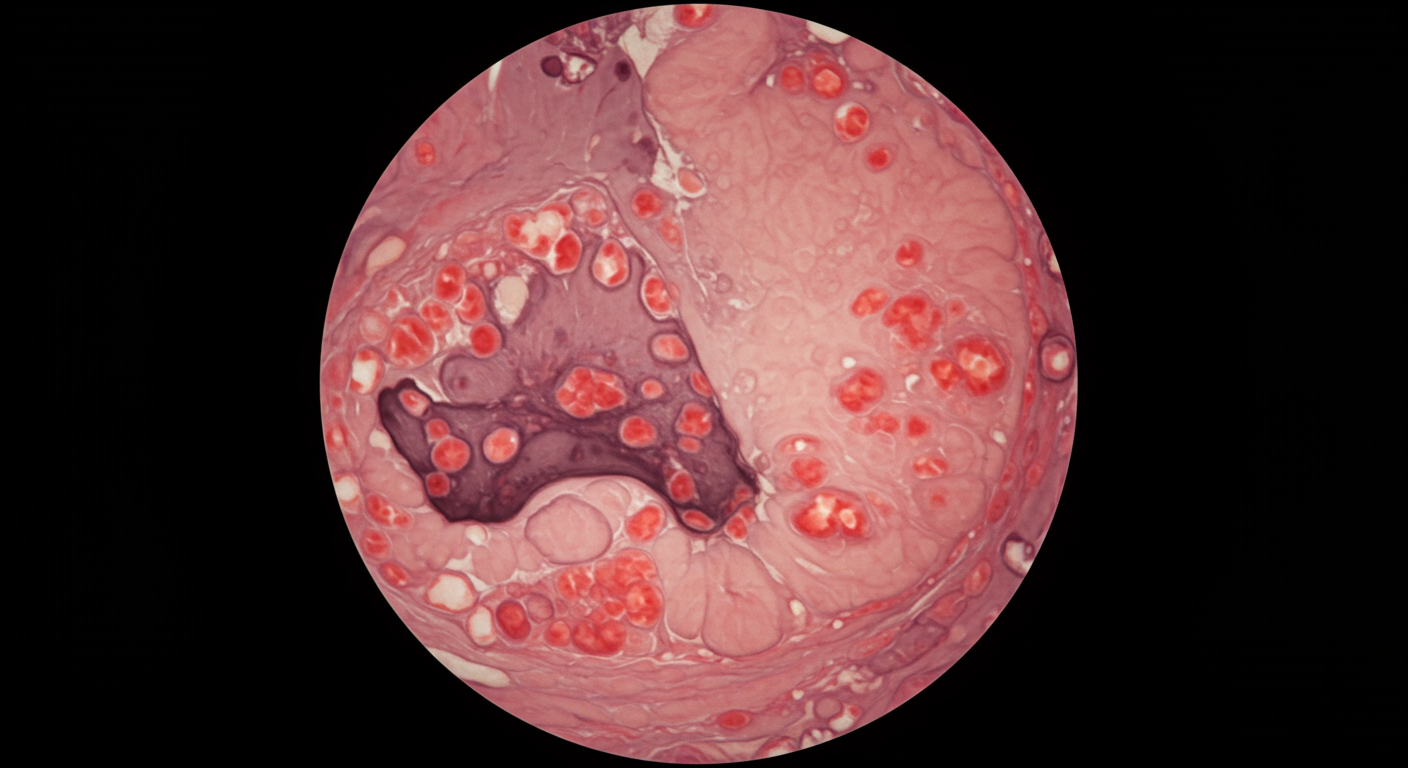

胃炎は胃の粘膜に炎症が起きた状態です。急性胃炎は突然発症し、慢性胃炎は長期間にわたって症状が続きます。ストレスが続くと、胃酸の過剰分泌や胃粘膜の防御機能低下により、胃炎を引き起こすリスクが高まります。

3. 胃・十二指腸潰瘍

ストレスが長期間続くと、胃酸の過剰分泌と胃粘膜の防御機能低下により、胃や十二指腸に潰瘍ができることがあります。潰瘍は粘膜が深く傷ついた状態で、強い痛みを伴うことが特徴です。

胃カメラ検査(胃内視鏡検査)を行うことで、胃炎や胃潰瘍、機能性ディスペプシアなどの診断が可能になります。